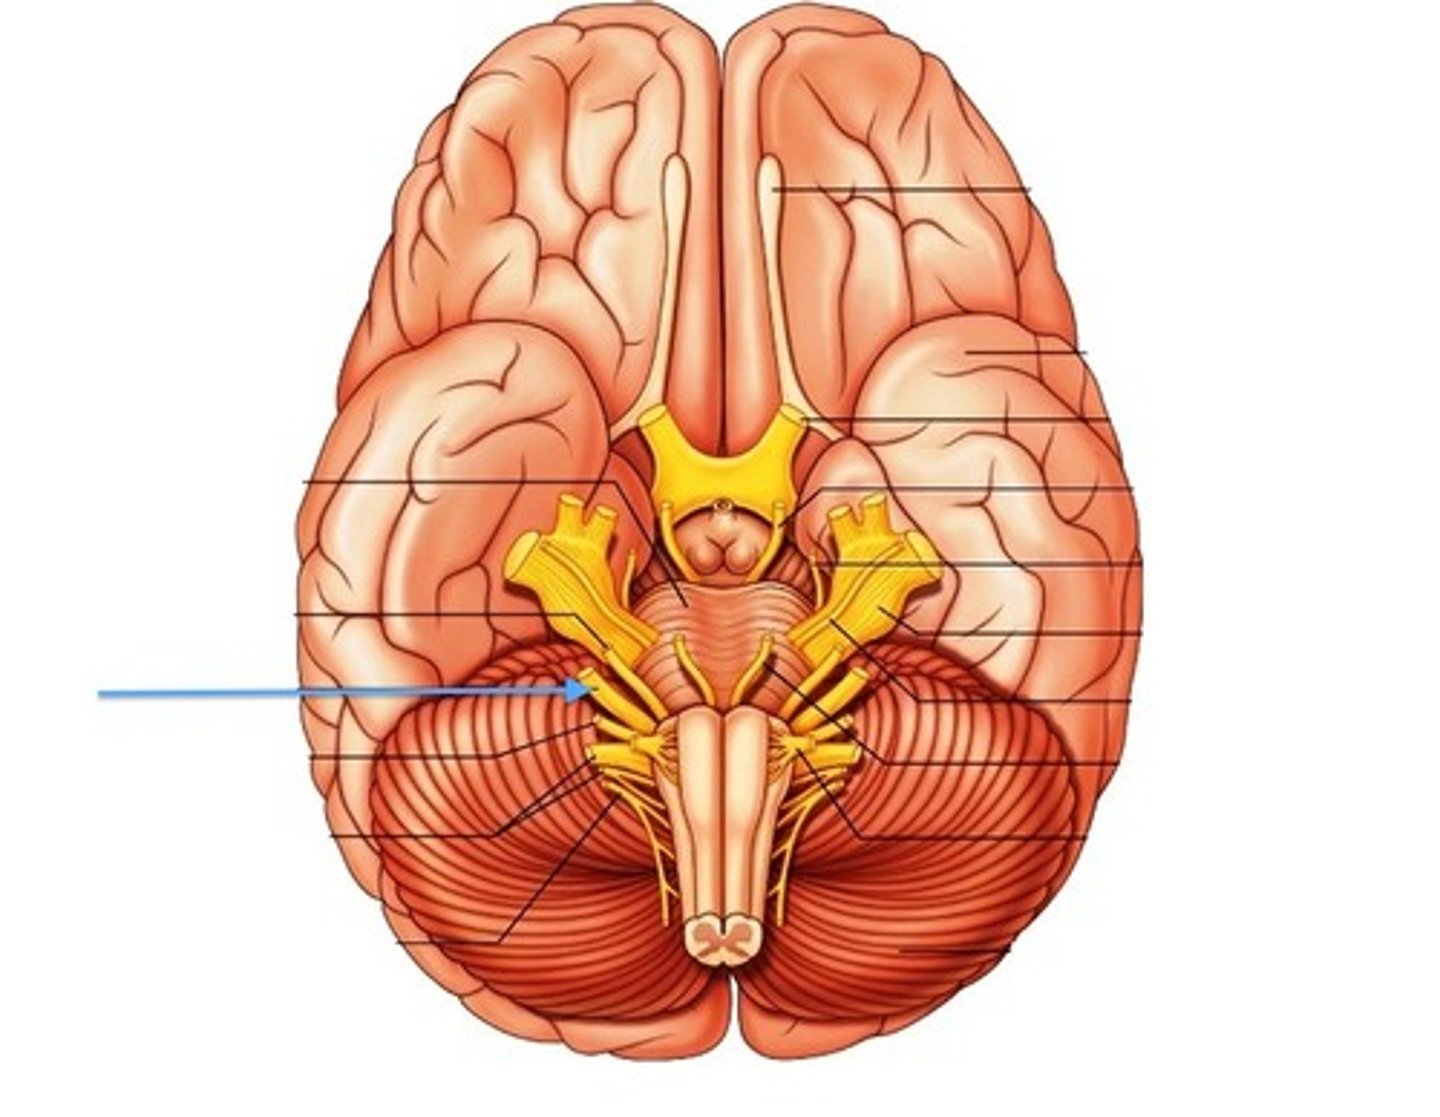

pons

center structure of the brain stem, located between the midbrain and the medulla oblongata

midbrain

or mesencephalon extends from pons to diencephalon. the pons is the center structure of the brain stem, located between the midbrain and the medulla oblongata

medulla oblongata

most inferior part of the brain stem; regulates breathing, heart rate, & blood pressure

cranial nerves

12 pairs of nerves that carry messages to and from the brain